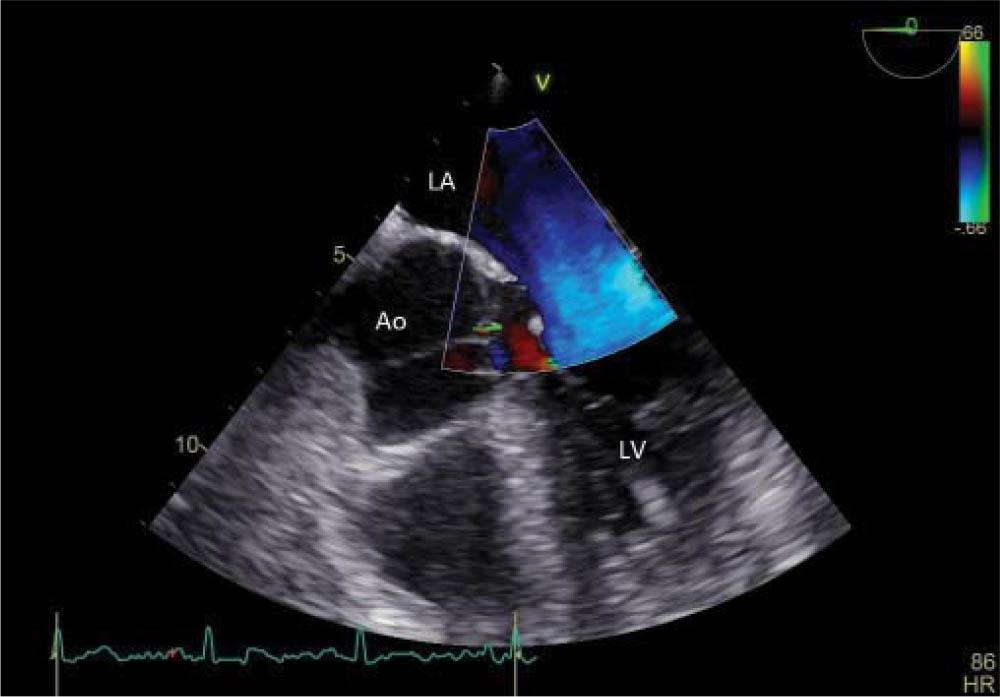

Transthoracic echocardiography (TTE) at admission and afterwards transesophageal echocardiography (TEE), both performed with GE Vivid E9, revealed a hyperechogenic mass, with independent movement, attached to the posterior mitral leaflet, on the atrial surface, with a diameter of 6/6 mm, prolapsing A2 scallop and mild mitral regurgitation (Figure 2). At the same time, it revealed a large mobile mass (diameter 18/4 mm) on the aortic valve, attached to all three leaflets (Figure 3), prolapsing in the left ventricular outflow tract (LVOT) (Figure 4) with high probability of non-coronary cusp (NCC) perforation without hemodynamic impact (Figure 5). Left ventricular size and ejection fraction were normal (Figure 6).

Figure 5

Transesophageal echocardiographymidesophageal 5 chamber view-perforation cusp without hemodynamic impact is revealed by colour Doppler examination.